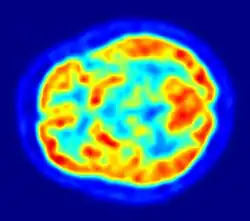

Although aphasiology is the historical core of neurolinguistics, in recent years the field has broadened considerably, thanks in part to the emergence of new brain imaging technologies (such as PET and fMRI) and time-sensitive electrophysiological techniques (EEG and MEG), which can highlight patterns of brain activation as people engage in various language tasks.[2][10][11] Electrophysiological techniques, in particular, emerged as a viable method for the study of language in 1980 with the discovery of the N400, a brain response shown to be sensitive to semantic issues in language comprehension.[12][13] The N400 was the first language-relevant event-related potential to be identified, and since its discovery EEG and MEG have become increasingly widely used for conducting language research.[14]

Hemodynamic

Hemodynamic techniques take advantage of the fact that when an area of the brain works at a task, blood is sent to supply that area with oxygen (in what is known as the Blood Oxygen Level-Dependent, or BOLD, response).[30] Such techniques include PET and fMRI. These techniques provide high spatial resolution, allowing researchers to pinpoint the location of activity within the brain;[2] temporal resolution (or information about the timing of brain activity), on the other hand, is poor, since the BOLD response happens much more slowly than language processing.[11][31] In addition to demonstrating which parts of the brain may subserve specific language tasks or computations,[20][25] hemodynamic methods have also been used to demonstrate how the structure of the brain's language architecture and the distribution of language-related activation may change over time, as a function of linguistic exposure.[22][28]